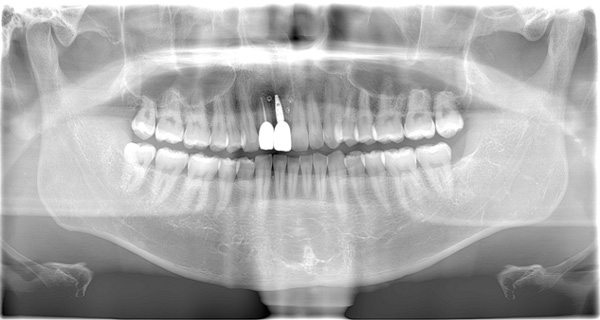

AFTER

| 年代・性別 | 50代 女性 |

|---|---|

| 主訴 | 左上のブリッジがグラグラして外れそう |

| 治療期間 | 約18ヶ月 |

| 費用 | 1,600,000円 |

| 治療内容 | インプラント、骨造成、サイナスリフト、セラミック修復 |

| 治療に伴うリスク | インプラント周囲炎 セラミックの破折、脱離 |